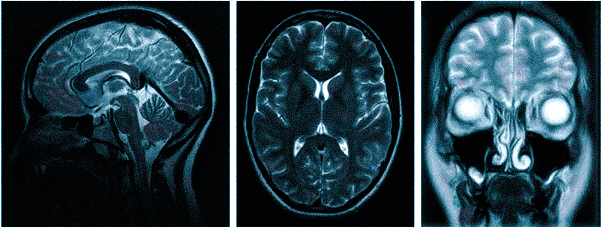

Магнитно-резонансная томография не менее точна, чем КТ, но ее область применения несколько иная. Она позволяет осматривать и диагностировать заболевания мягких тканей мозга и показывает результаты в трех плоскостях:

- Аксиальная (горизонтальная проекция)

- Фронтальная (прямая проекция)

- Саггитальная (боковая проекция)

МРТ позволяет очень четко увидеть проблемы с мягкими тканями: новообразования доброкачественные и злокачественные (рак) (их форму, локализацию и объем), нарушения работы гипофиза, нервные и мышечные волокна. Таким способом можно увидеть и измерить объемы отеков, опухоли нервной системы и другое. Кости же отображаться будут опосредованно.

МРТ при головных болях (в трех проекциях): специальная программа выстраивает объемные изображения полученных срезов, что позволяет увидеть даже мельчайшие изменения и отдифференцировать патологию от нормы